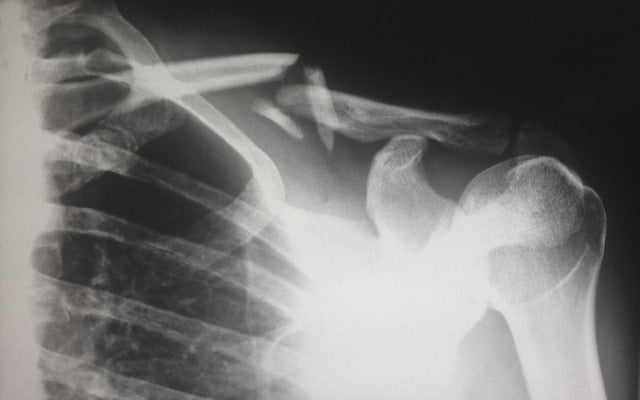

• Innovations: Tesla was one of the first scientists to experiment with X-Ray imaging, independently making discoveries around the same time as Wilhelm Röntgen. Tesla experimented with various types of tubes and even cautioned the scientific community about the dangers associated with X-ray radiation.

• Legacy: Tesla’s early X-ray images, which included parts of the human body, marked significant advancements in medical diagnostics. Although not as celebrated as Röntgen, Tesla’s contributions to the development of radiology have been invaluable.